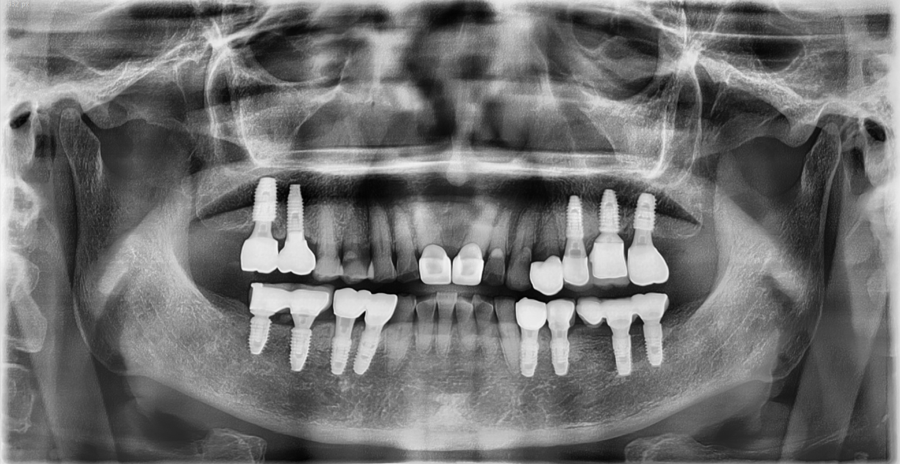

This is a case in which function and appearance were restored through implant treatment after extraction.